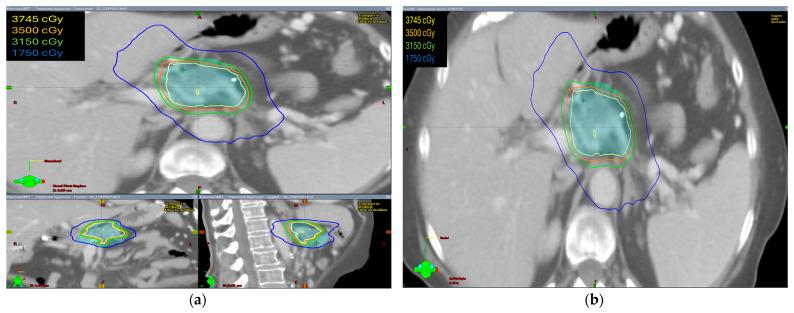

We conducted a retrospective review of patients treated with SBRT using abdominal compression (AC) or an end-expiratory breath-holding (EEBH) technique. The median prescribed dose was 35 Gy, delivered in five fractions. Toxicities were recorded using Common Terminology Criteria for Adverse Events (CTCAE) v5.0, and survival was estimated using the Kaplan-Meier method.

我们对采用腹部压缩(AC)或呼气末屏气(EEBH)技术进行 SBRT 的患者进行了回顾性研究。中位处方剂量为 35 Gy,分 5 次给予。采用 CTCAE v5.0 记录毒性,采用 Kaplan-Meier 法估计生存情况。